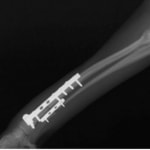

トイプードル 右遠位橈尺骨短斜骨折のALPSによる内固定

当院ではAdvanced Locking plate system(ALPS)と、Locking compression plate system(LCPS)という骨接合法で骨折症例の治療を行っています。

LCPは、スクリュー(ネジ)とプレート(金属の板)をロックする特殊な構造により骨折部位を固定する新しい世代のプレートシステムです。ひとつのホールでロッキングスクリューとスタンダードスクリューの使用を選択できるユニークな構造をしているため、骨折断端間の圧迫を目的とした従来型プレート固定法に加え、高い角度安定性を有するロッキングスクリューを用いた固定法の選択が可能です。従来のプレートシステムでは困難だった部分の骨折や癒合不全の症例に高い治療効果をもたらします。